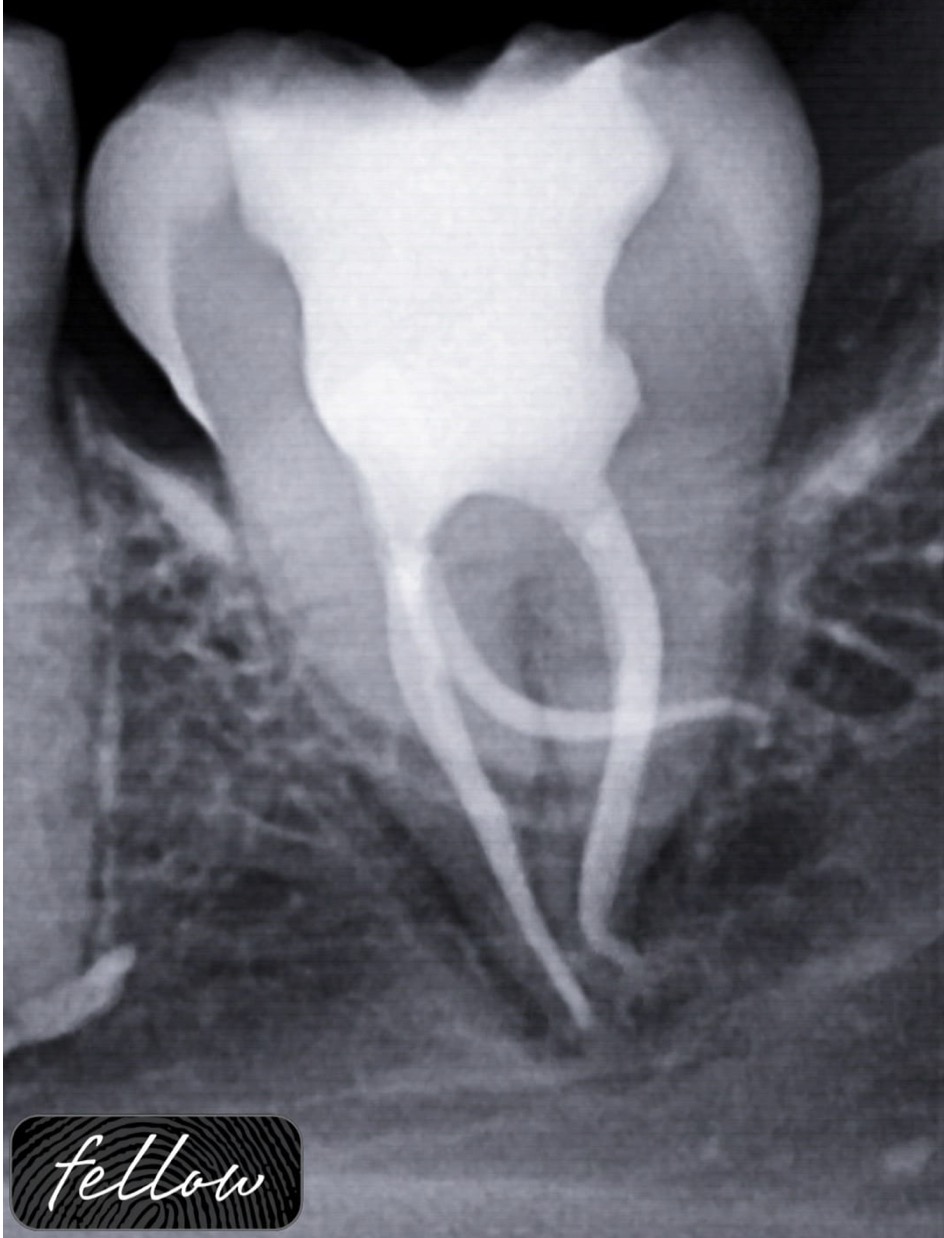

Management of cervical Perforation, Apical abscess and huge periapical lesion

Root perforation is a complication of Endodontic treatment characterized by the communication between the root canal space with the periodontal tissues. These accidents usually occur due to iatrogenic causes including lack of knowledge of dental anatomy, wrong endodontic access, calcification of the coronary and cervical thirds, failure in radiographic analysis. Among the factors that affect root perforation prognosis are the location (cervical, middle and apical thirds), the extent, presence or absence of periodontal pockets, the time between perforation and treatment, biological compatibility and sealing ability of the filling material.